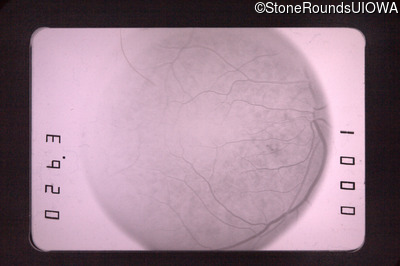

Fluorescein Angiography - Left - 20/30 -3

Exemplar